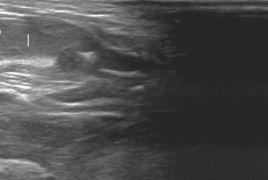

Il est important de noter que n'importe quelle maladie peut se traduire sous cette forme. L' échographie abdominale fait partie des examens complémentaires de choix pour comprendre et déterminer les causes de la stase

Les lapines peuvent présenter de l'abattement et des pertes de sang (parfois spectaculaires). Elles présentent parfois des grossesses nerveuses (pseudogestation) associées au développement de la tumeur utérine. Le diagnostic se fait par échographie, d'une part pour confirmer la présence de la tumeur mais aussi pour faire un bilan d'extension et vérifier l'absence de métastases abdominales sur le foie ou la paroi abdominale. En cas de confirmation de tumeur, une radiographie thoracique doit systématiquement être proposée pour rechercher des métastases pulmonaires.

Le diagnostic se fait par échographie. Le traitement est chirurgical. Une technique d'ovariectomie par les flancs est généralement préférée en l'absence de tumeur utérine, elle est de bon pronostic.